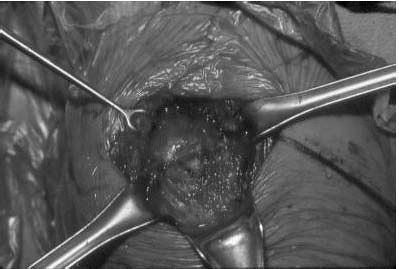

precipitously to 14% for stage IV osteonecrosis.

shoulder arthroplasty, may be appropriate in stage IV and V disease and

select patients with stage III involvement (Figure 12-13). Glenoid resurfacing is used when the glenoid is involved with substantial secondary arthritis. In a recent study, 88

![]() |

|

FIGURE 12-13. Intraoperative photograph of avascular necrosis of the humeral head. Note the collapse of the articular surface.